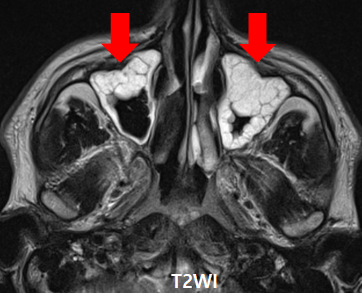

Case Study: A 15-year-old girl presented with a headache and chronic nasal congestion.  Paranasal Sinusitis

1.  A 15-year-old girl presented with a headache and chronic nasal congestion

2. A CT coronal section through the paranasal sinuses was obtained.

1. Both ethmoid and maxillary sinus mucosa are thickened (arrow).

2. This is a case of pansinusitis.